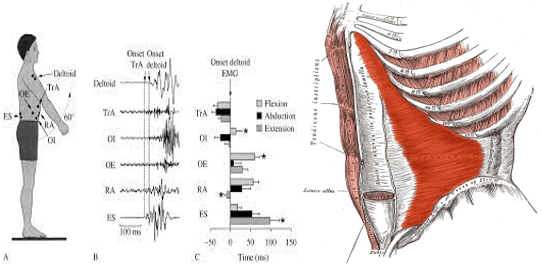

1990년대에 퀸즈랜드 대학의 hodges외 연구원들은 특유의 척추의 운동조절장애

( motor control dysfunction)는 요통과 연관이 있다고 주장했습니다.

(Hodges and Richardson,,1999).

이에 따르면 증상이 없는 일반인에 비해 요통환자들에게서 상지나 하지의 운동시

복횡근의 선행적인 조절(Ancipatory Stabilioty)과 복횡근의 동원 지연이

(delayed activation 일어나는현상이 빈번하게 발견되어졌다고 언급하였습니다.

그래서 이후에 많은 운동요법/재활 프로그램들이 연구의결과에 의해 복횡근

transverse abdominus (TA) 을 단독으로 훈련시키는 방향으로 많이 수정되어졌습니다.

요추의 안정성은 복횡근(Tr.a)하나의 근육이 아닌, 오케스트라의 하모니처럼

여러 다른 근육들 의 상호작용 속에 유지되어진다는 개념으로 확장되기 시작하면서

개별적인 근육의 안정화가 아닌 각각의 다양한 운동의 종류에 따라 각 근육의 역할 비중은

커지거나 작아질 수 있다고 언급하고있습니다. (Kavcic 2004).